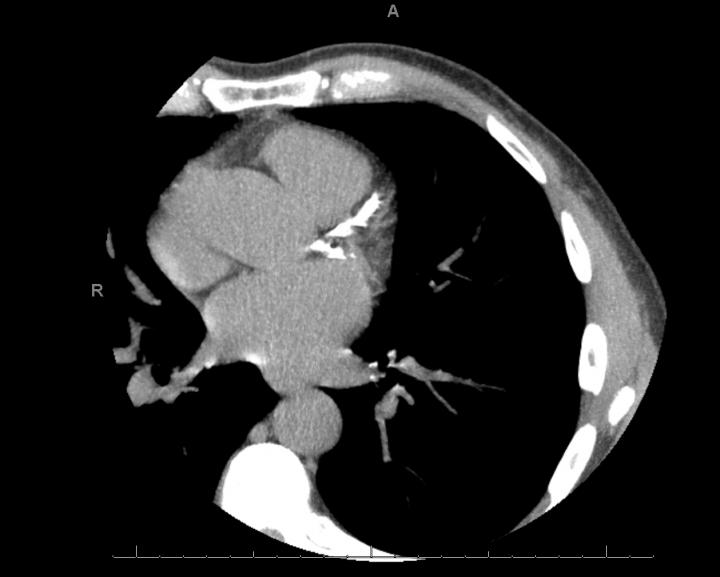

image: Coronary artery calcium scans, such as one shown here, are used to detect the amount of calcium lining the heart's arteries and assess the risk of heart attack or stroke.

In the study, Khera and his colleagues looked to a diagnostic test - coronary artery calcium (CAC) scanning - to see if it could help doctors make this important decision. CAC scanning, a CT scan that scores the amount of calcium that lines the heart's arteries, is commonly performed to detect hardening of the arteries and risk of a heart attack or stroke.